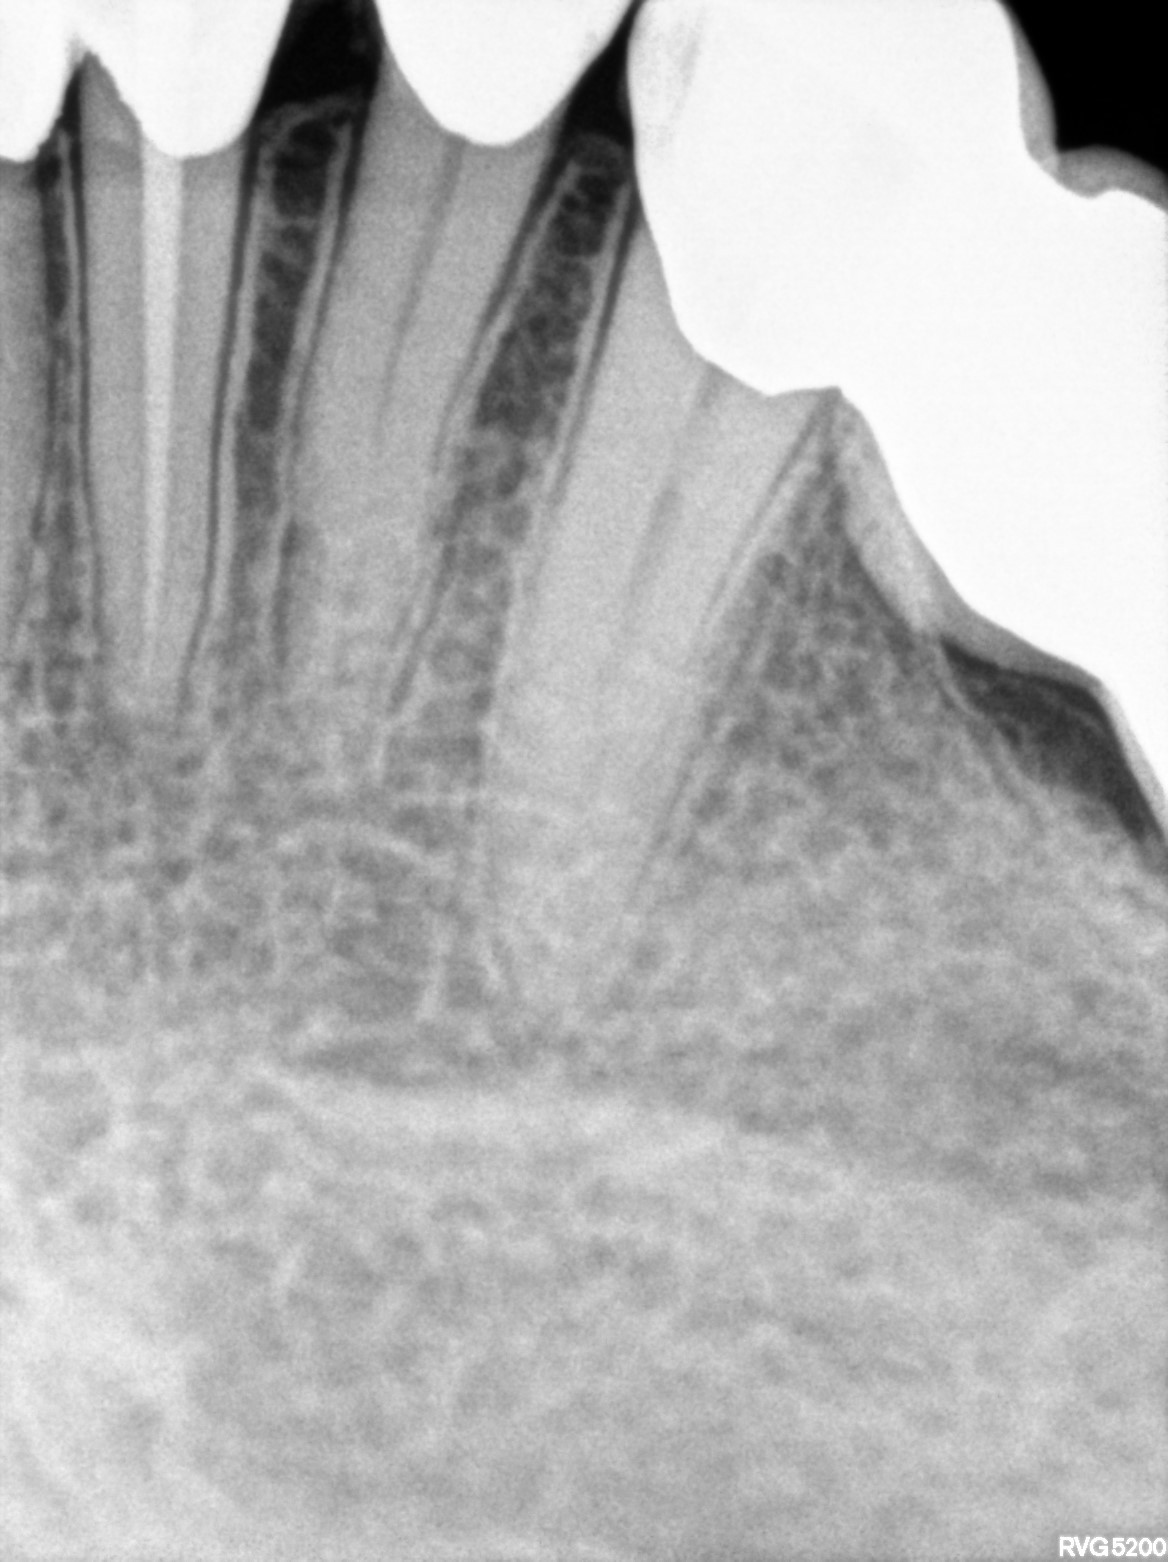

Dental Radiographs FHIR: DocumentReference · LOINC 24641-7

xray_1763362538_0.jpg

24641-7